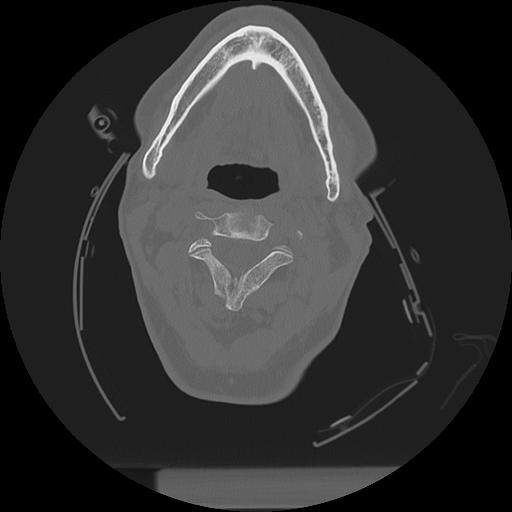

11 HUESO,,Axial,2.0,HUESO,,